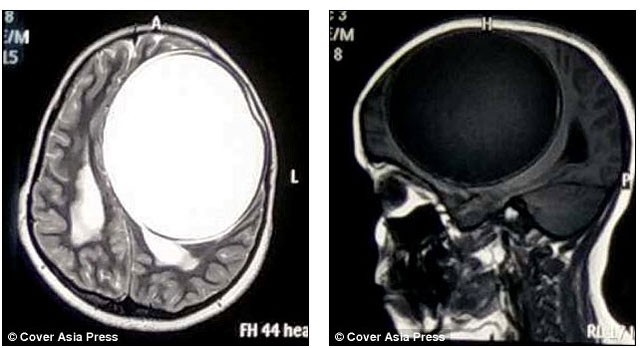

Sık sık nöbet geçiren ve bir tarafı felç olan 12 yaşındaki kızın hastalığının sebebi doktorları şoke etti. 12 yaşındaki hintli nita juggi sürekli nöbet geçiriyor ve son 12 aydır vücudunun bir tarafı felçli haldeydi.

Doktora başvurduktan sonra yapılan çeşitli tetkikler sonrasında küçük kızın beyninin yarısını kaplayan tenya yani bağırsak kurdu larvalarından kaynaklı merkezi sinir sisteminde sistiserkoz teşhis edildi.

Bir bağırsak kurdunun larvasının sebep olduğu kist greyfurt büyüklüğünde ve her an patlayıp ölüme sebep olabilecek boyutlardaydı. başarılı bir ameliyatla beynindeki kist alınan kız şuan iyileşme sürecinde.